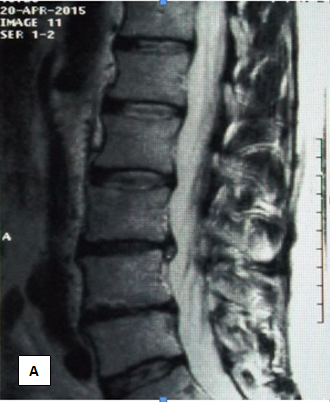

Clinical examples

Sick F, 44 years old, n stumble In February 2015, after months of unsuccessful treatment by a neurologist with complaints of acute pain, radiating to the right n izhnyuyu limb. He notes periodic weakness in his right leg, a limp. When examining antalgic scoliosis to the left, the relative shortening of the right leg. With th Lassega right 15 degrees, VAS 7-8 points. MRI of predelyaetsya dorsal sided medial-paramedian disc herniation L3/L4, with a tendency to sequestration of up to 0.8 cm, extending to the right intervertebral foramen, with its contraction, having caudal spread sequestering component along the body of L4 vertebra to 0.5cm in the right lateral pocket, with compression of the right nerve root, compressing adjacent sections of the dural sac (Figures 1A & 1B).

Figure 1 Patient F. MRI examination before treatment.